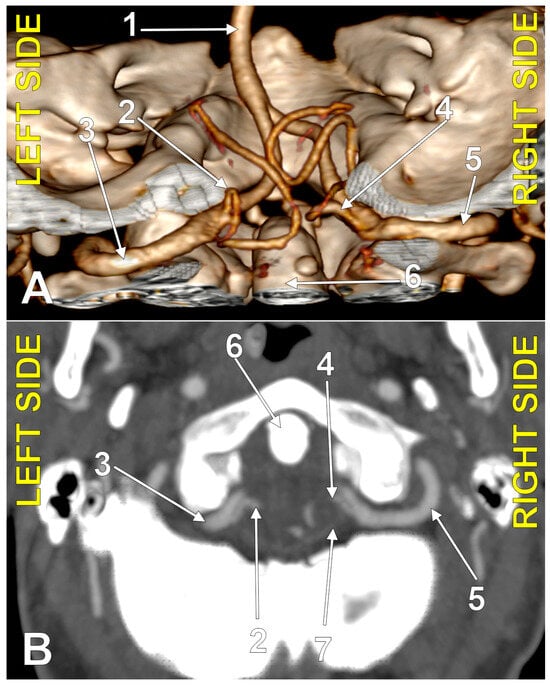

4.3. Extradural Origin of the PICA

4.4. Transdural Origin of the PICA